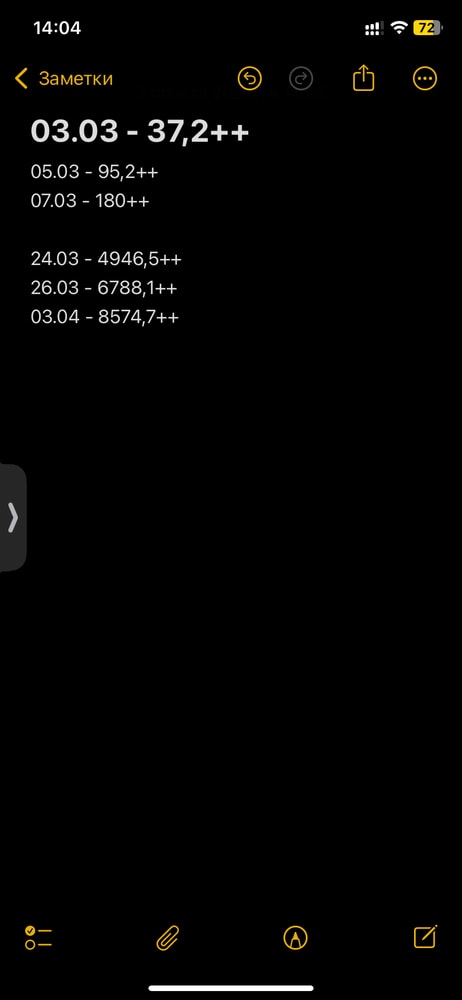

делала узи кроме пя ничего не увидели, переделала через 7 дней, за неделю выросло из 10,0 мм в 14,0 мм. Хгч отправили сдавать сдала, буду снова смотреть в динамике. Но прогноз не самый лучший. Говорит гинеколог, что если падает то аборт делать… была поздняя овуляция, читала что эмбрион виден от хгч 10 тыщ

Не поняла о какой поздней овуляции идёт речь, но у вас точно какой-то вид замёрзшей, по УЗИ больше похоже на анэмбрионию. ХГЧ за месяц дорос до 8500 тысяч, понимаете, что при нормальной Б он через неделю такой был бы.

У меня хгч за 7 дней вырос с 1650 до 29226. Ещё за 6 дней с 29226 до 70505. Итого за 13 дней с 1650 до 70505.

ПЯ с 6 мм до 22.6 мм выросло за 12 дней.

У вас за у вас за 27 дней хгч выросло со 180 до 8574. И пя растёт медленно. по 1 мм в день надо бы.